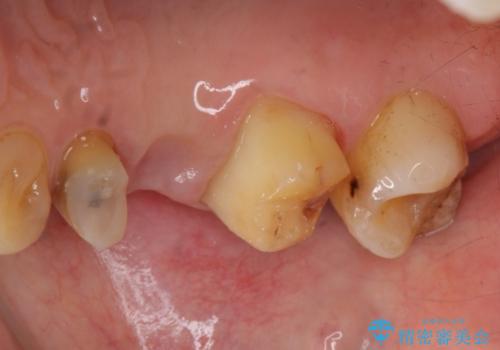

- 他院でブリッジの仮歯を入れたが、外れやすいため転院を希望された患者様です。

支台歯の形が角度が大きくついた形に形成してあり、外れやすい形になっていたため修正してから歯型をとりました。

- 36.3万円(ジルコニアクラウン10万円x3本)費用は治療当時の料金となります

根の治療のやり直しは特に行っていません。